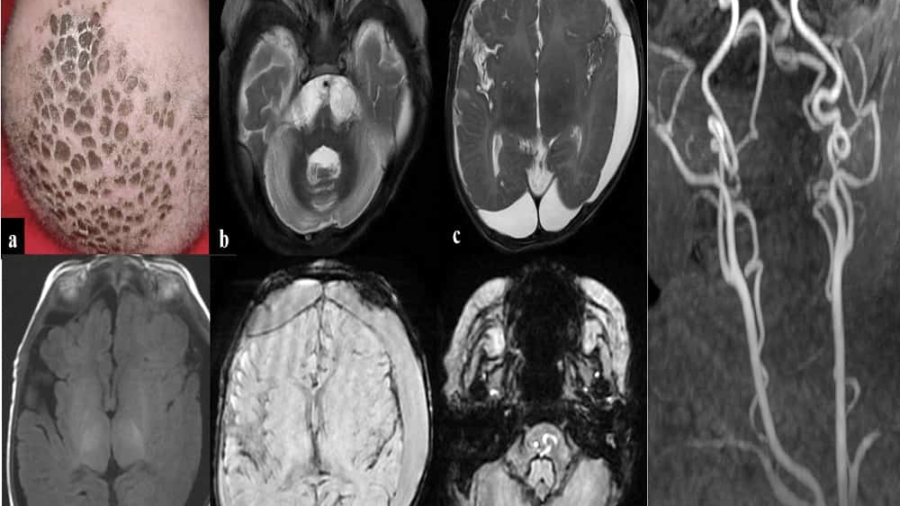

A 5month old male child born out of by non-consanguineous marriage presented with history of left focal seizure, reddish discoloration of left hand and delayed attainment of milestones. Parents also noticed increase in fairness of the baby and loss of hair.